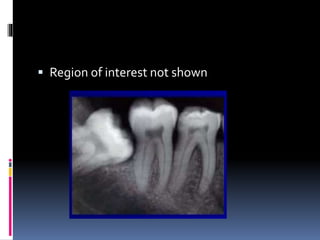

 Region of interest not shown